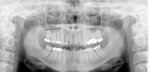

nun wollt ich mal Rückmeldung geben, was sich bisher getan hat und somit können wir auch ein wenig Licht in das bringen was Ihr auf dem Röntgenbild gesehn habt.

Der 12 er ist seit Mitte Dezember raus, hatte vorher und hinterher das von der Hp empfohlene Entkoppeln machen lassen. Habe auch vor dem Ziehen noch mit MSM, Chlorella und einem homöopath. Mittel begonnen.

Aber es kamen neue Probleme: mein Kiefer macht seitdem besonders rechts Probleme, mein tiefer Biss und die verschobene Mittellinie wurde nun erst richtig auffällig und es gibt arge Probleme nun einen passenden Zahnersatz zu finden. Das Provisorium hielt leider nicht lang und seit letzter Woche hab ich ne Prothese, die aber bis jetzt nicht gut sitzt und so laufe ich bisher mit Zahnlücke rum.

Dann wurde letzte Woche mit der Sanierung der restl. Zähne begonnen. Meine Zahnärztin sah bereits von aussen Karies, die 3 Kollegen vorher nicht gesehn hatten. Der 46 war massiv von Kaies befallen unter meinem tollen Inlay, so dass sie gar nicht alles entfernen konnte, sonst hätts wohl den Nerv getötet. Nun hab ich für 10 Wochen son Medikament drin und dann hoffe ich dass es wieder gut ist. 45 und 25 war auch kariös, aber es ging noch. Hab da überall prov. Füllungen aus Zement und etwas Kunststoff drin ( kinesiol. getestet ) nur Zement hat wohl nicht gut getestet.

Der 15 ist noch dran.

Von meinem 26er hab ich mir die tolle Palladiumkrone ( Argedent 65 SF ) entfernen lassen und der ist momentan mein Sorgenkind. Selbst mit Spritze war der Schmerz beim Schleifen nicht auszuhalten, obwohl die Zahnärztin meint von oben säh der Zahn noch gut aus, bei weitem nicht so schlecht wie der 46er. Also er lebt, aber wieeeeeeeeeeeeeeeeee

. Nun ist ne Prov. Krone aus Kunststoff drauf und noch immer hab ich Schmerzen nach dem essen, nach Druckbelastung, z. Teil bei kalten Temp. oder im Bett. Ich vermute nun dass der Zahn bzw. Nerv aber schon ne chron. Entzündung hatte, die nun durch das Bearbeiten wieder akut ist. Er blutete sehr stark, was er aber lt. Akte auch beim Einsetzen der Palladiumkrone vor 7 Jahren schon tat. Und immer wieder hatte ich zw. 25 und 26 ein Gefühl von Entzündung und Zahnfleischbluten, nun ist der Schmerz nur tiefer und um ein vielfaches stärker. Nunja, ich nehme weiter homöopath. Mittel und hoffe, dass der Zahn sich erholt und zu retten ist. Bin grad nicht so ganz sicher.

Des weiteren werde ich eine Aufbissschiene bekommen und hoffe dass mein Kiefer sich noch was richten lässt, denn so is er ne wahre Katastrophe.....aber auch das is wohl nie einem Zahnarzt aufgefallen und mir auch nicht bis dieser eine Zahn, der wohl alles noch halbwegs stabilisierte, nun fehlte.